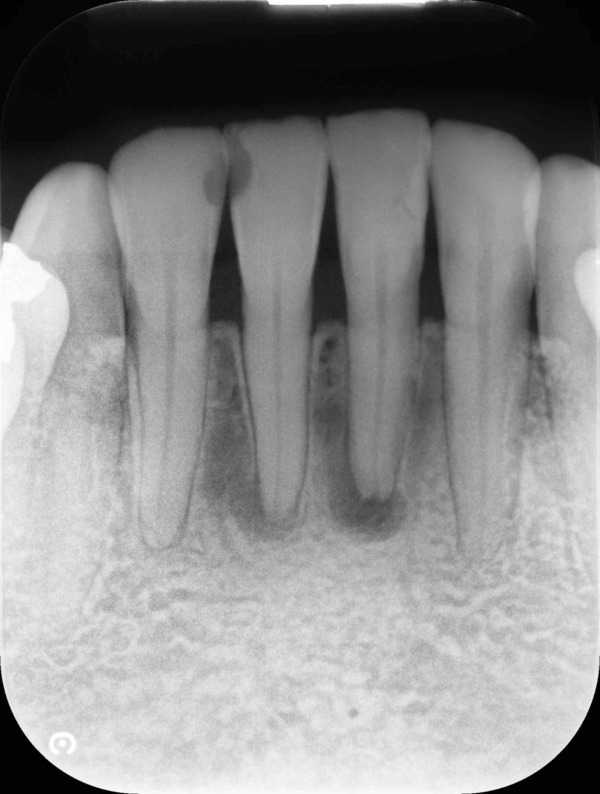

術前のデンタルX線写真と口腔内写真です。左下の一番奥の歯(#37)です。

左下の親知らずは1ヵ月ほど前に抜いたそうです。

親知らずと隣り合っていた歯の後ろ側(遠心)から虫歯が進行しています。

診査の結果、神経は正常に生きていることが分かりました。その為、いきなり神経は取らずに虫歯を取り切った上で神経を温存する治療を進めていくこととなりました。